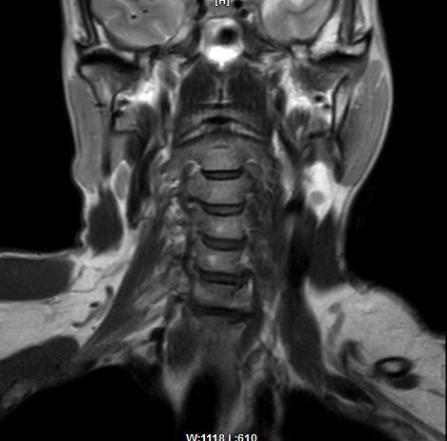

马德龙病的影像表现为颈项部等处脂肪组织蓄积增厚,可累及皮下或肌肉间隙,脂肪蓄积处没有包膜形成,蓄积脂肪内可有线状或网状纤维间隔,病变常常左右对称,颈部肌肉可受压、变细,蓄积脂肪组织内可有钙化或骨化。

刀某颈部MRI